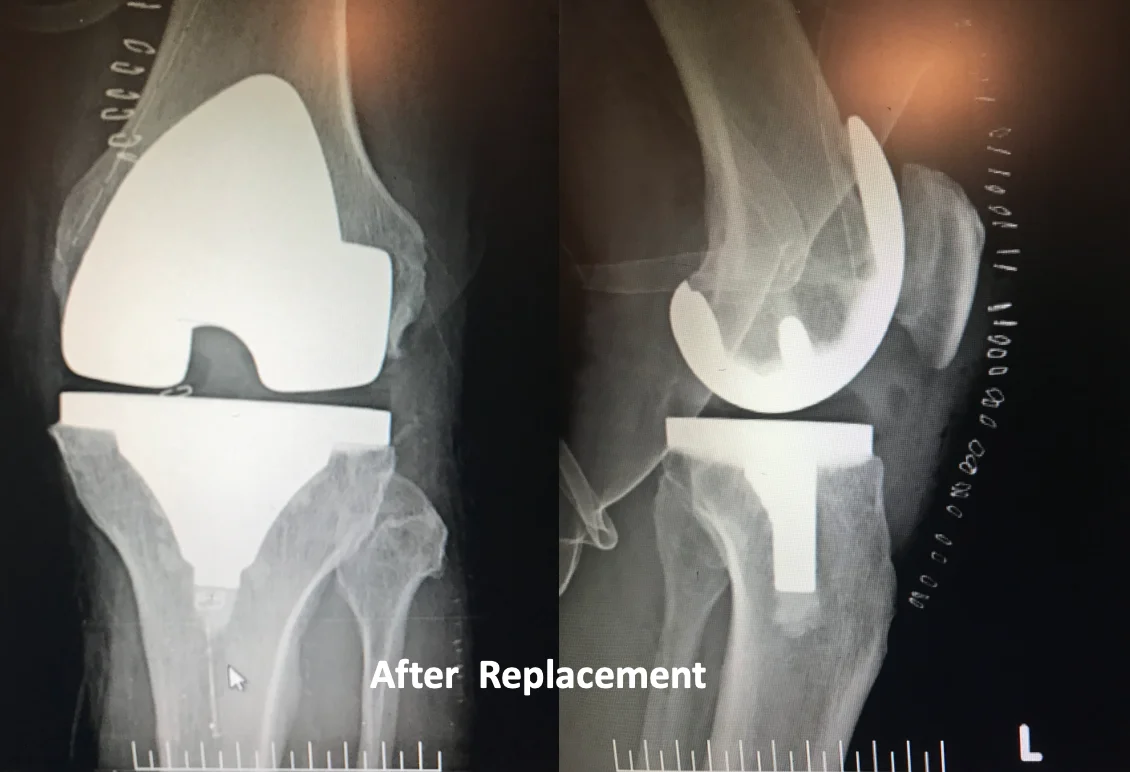

Knee replacement surgery (knee arthroplasty) involves replacing the damaged surfaces of your knee joint with an artificial implant.

How the Surgery Is Performed

During knee replacement surgery:

Robotic assistance may be used to ensure accurate alignment and a well-balanced knee.